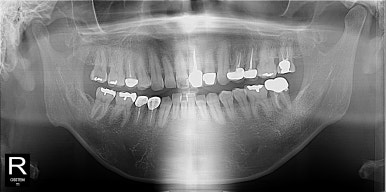

발레리나 친구들~ 무대에 서는 친구들이라 외모에 민감하고 특히 돌출과 비대칭때문에 사진 찍을 때 신경이 많이 쓰인다고 했다. 사실 골…

27세 여자 환자 좌측 제2대구치를 발치해야한다는 진단을 받고 상담 중 사랑니를 교정해서 위치시키고 써보자고 얘기했다~ 수술을 …